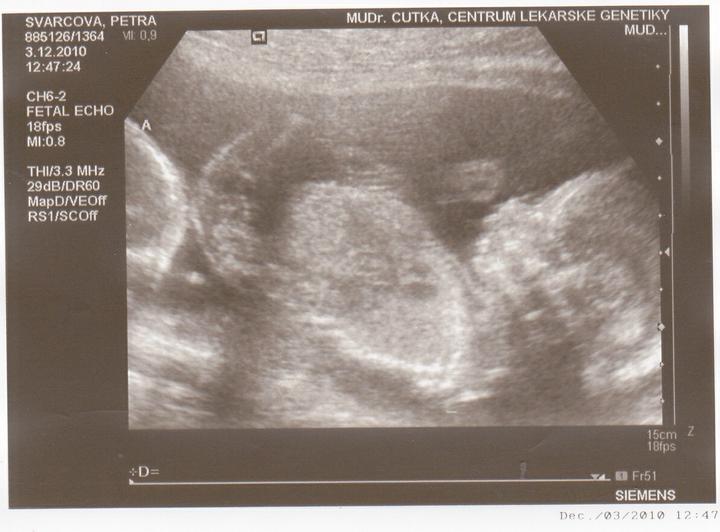

3.12-Jedu do Českých budějovic na ultrazvuk.Jsem zvědavá jak miminka povyrostly za ten měsíc co jsem tam byla naposled.Ale zároveń se bojím jestli jsou v pořádku.

Včera jsem Byla v Českých Budějovicíh.Jedno mimi váží 267g, a druhé váží 314g.A jsou to kluci.